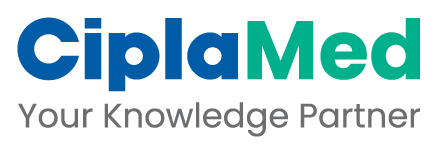

Human immunodeficiency virus (HIV) causes a chronic infection that leads to profound immunosuppression. A

hallmark of this process is the depletion of CD4 lymphocytes, and this predisposes the patient to develop a

variety of opportunistic infections and certain neoplasms.

The course of the infection may vary, with some individuals developing immunodeficiency within 2 to 3 years and

others remaining asymptomatic for 10 to 15 years. A typical course spanning over about 10 years is depicted in

the following chart:

Thus, the CD4 T-lymphocyte count is the best-validated predictor of the likelihood of developing an opportunistic

infection. Susceptibility to opportunistic infections increases as HIV-induced immunodeficiency becomes more

severe.